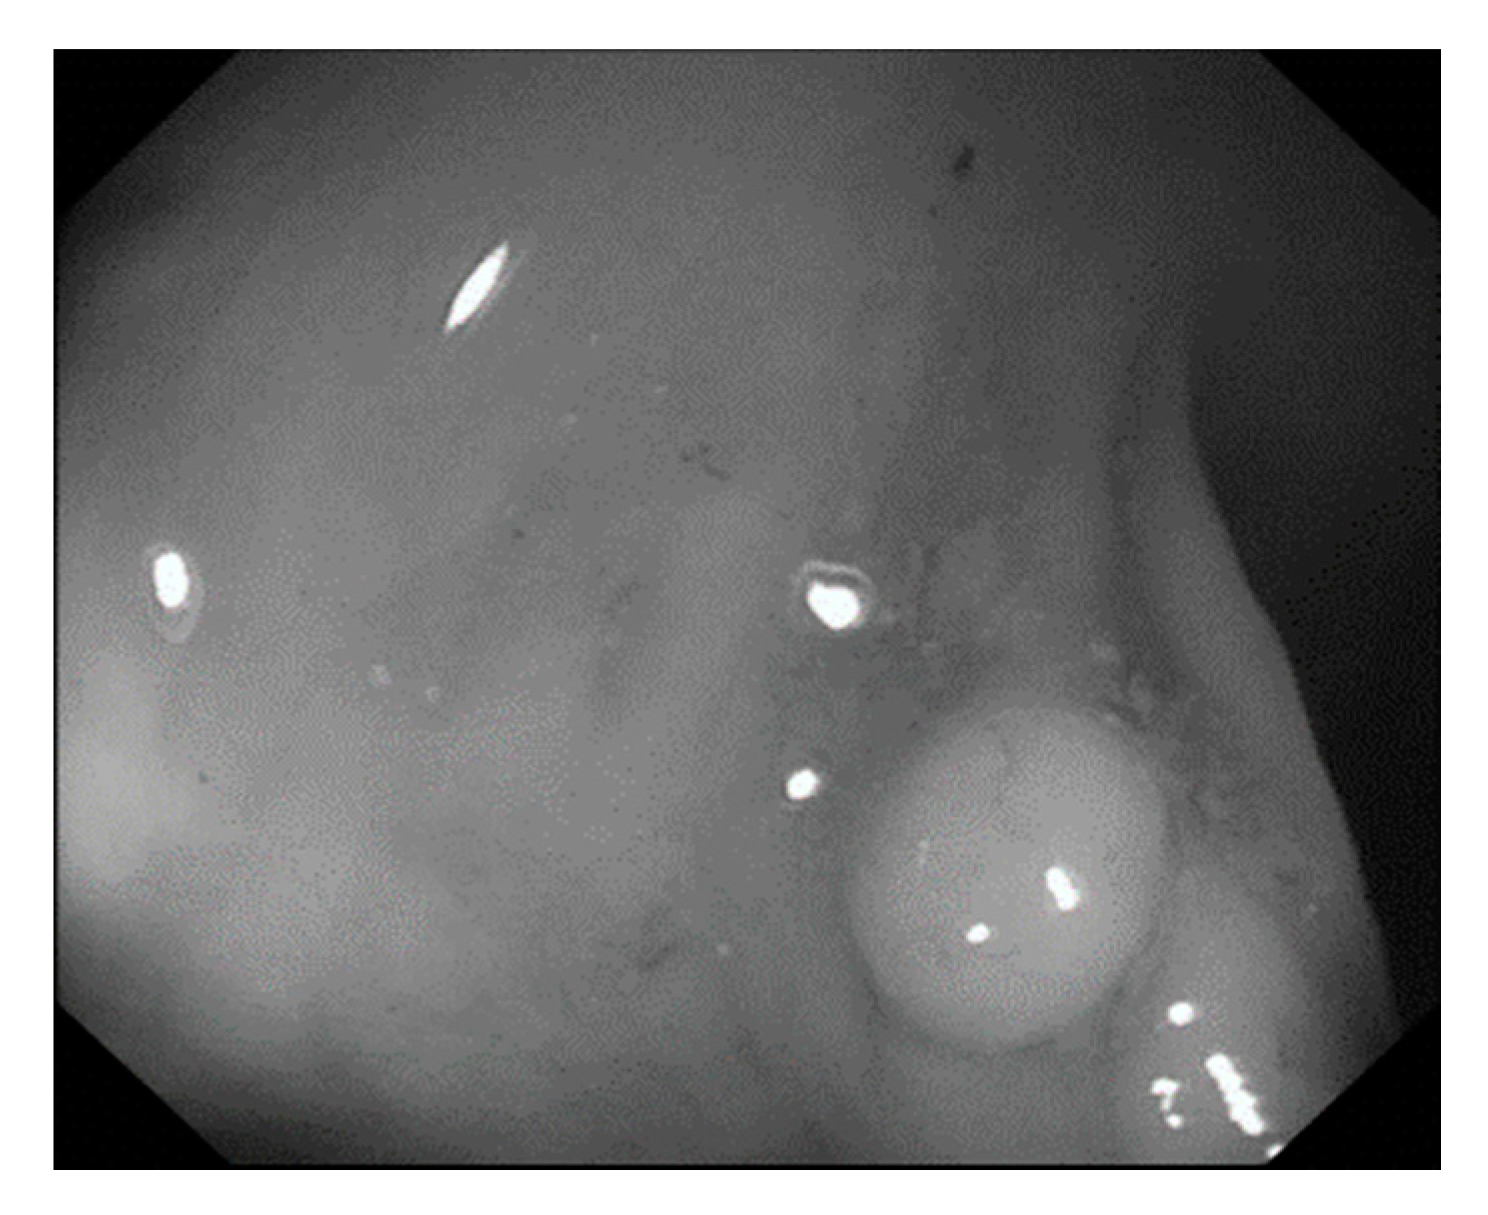

Currently, many medical images are processed into grayscale images, such as ultrasound, computed tomography (CT), and magnetic resonance (MR) images. Tan et al. [44] applied a gray-level cooccurrence matrix and CNN to CT images for polyp diagnosis. Zhang et al. [45] compress the three-channel color images of chest CT to grayscale images. A five-layer deep CNN with stochastic pooling is used to diagnose chest-based COVID-19. Xie et al. [46] mentioned that in deep learning, colors are not the key features influencing accurate image classification. They also discovered that in X-ray image classification, the speed and accuracy of processing grayscale images were considerably higher than those of processing RGB images. The grayscale method used was ITU-R Recommendation BT.601 [47]. Moreover, misjudgments were easily made in the presence of excessive intestinal wall textures, when polyps were too small (Figure 2), and when polyp textures were similar (Figure 3) to intestinal wall textures.

Figure 3. Small texture of polyp and intestinal wall.